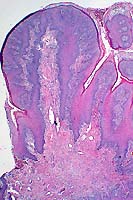

20x

obj

- Case 7-3. Placenta. Trophoblastic cells are detached

from the surface of the fetal placenta and placenal villi. The

intervillus space contains abundant necrotic cellular debris,

scattered yellow-orange pigment (meconium), and occassional macrophages

and neutrophils. Villous connective tissue is thickened and hyalinized.

40x

obj H&E

- Case 7-3. Lung. There are abundant coccobacilli

and fewer neutrophils filling scattered bronchioles. Occassional

plump macrophages contain bacteria which compress the nucleus

against one pole of the cell. The interstitium is expanded by

macrophages, fewer lymphocytes and fibroblasts admixed with finely

granular proteinaceous debris.

obj B&H stain

- Case 7-3. Lung. Brown and Hopps staining demonstrate

aggregates of Gram positive bacilli within many of the bronchioles.

Periarteriolar connective tissue is expanded by clear space (edema).